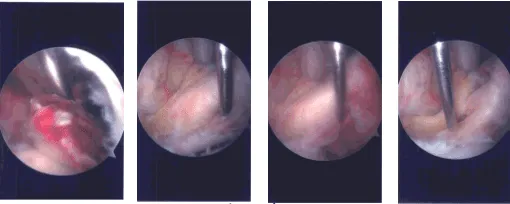

The tourniquet was elevated after exsanguinating the limb. Lateral entry portal was made. Arthroscope was inserted. Examination of the patellofemoral compartment showed no cartilage damage. Examination of the medial tibiofemoral compartment showed no meniscus or cartilage tear.

The Medical entry portal was made with the use of a spinal needle. Examination of the anterior patellar notch showed that avulsion of the ACL from the tibial attachment with raw bone. It was thoroughly irrigated and drained.

Examination of the lateral tibiofemoral compartment showed tearing of the anterior horn of the lateral meniscus in line with the ACL along with the intermeniscal ligament. It was decided not to repair the lateral meniscus because it was falling in line once the reduction of the ACL fragment was done.

The ACL fragment was reduced in its place and held with the use of a tibial tray. A #2 FiberTape was passed with the use of labral Scorpion through the posterior fibers of the distal ACL. This was followed by passage of a 1.3 mm Suture Tape in the same vicinity to achieve good hold on the ACL ligament.

The fragment was again held with the tibial ACL ring and a Beath pin was passed through the separate incision distally from the tibia into the knee joint. The sleeve was removed, but the ACL ring was kept in place to keep the fragment in place. A 4-mm cannulated drill was passed over the Beath pin and the Beath pin was removed.

Now, suture passer was passed through the cannulated drill and the cannulated drill was removed. The four tails of the sutures were noted on to the suture retrieval lasso and passed out of the tunnel. Once they were out, a good reduction of the ACL could be seen. There was no laxity of ACL.

All the four tails of the suture were put into the tibia with the use of 4.75 SwiveLock after drilling and tapping. A good reduction was achieved Final picture was taken and saved.

Intraoperative Arthroscopy Images